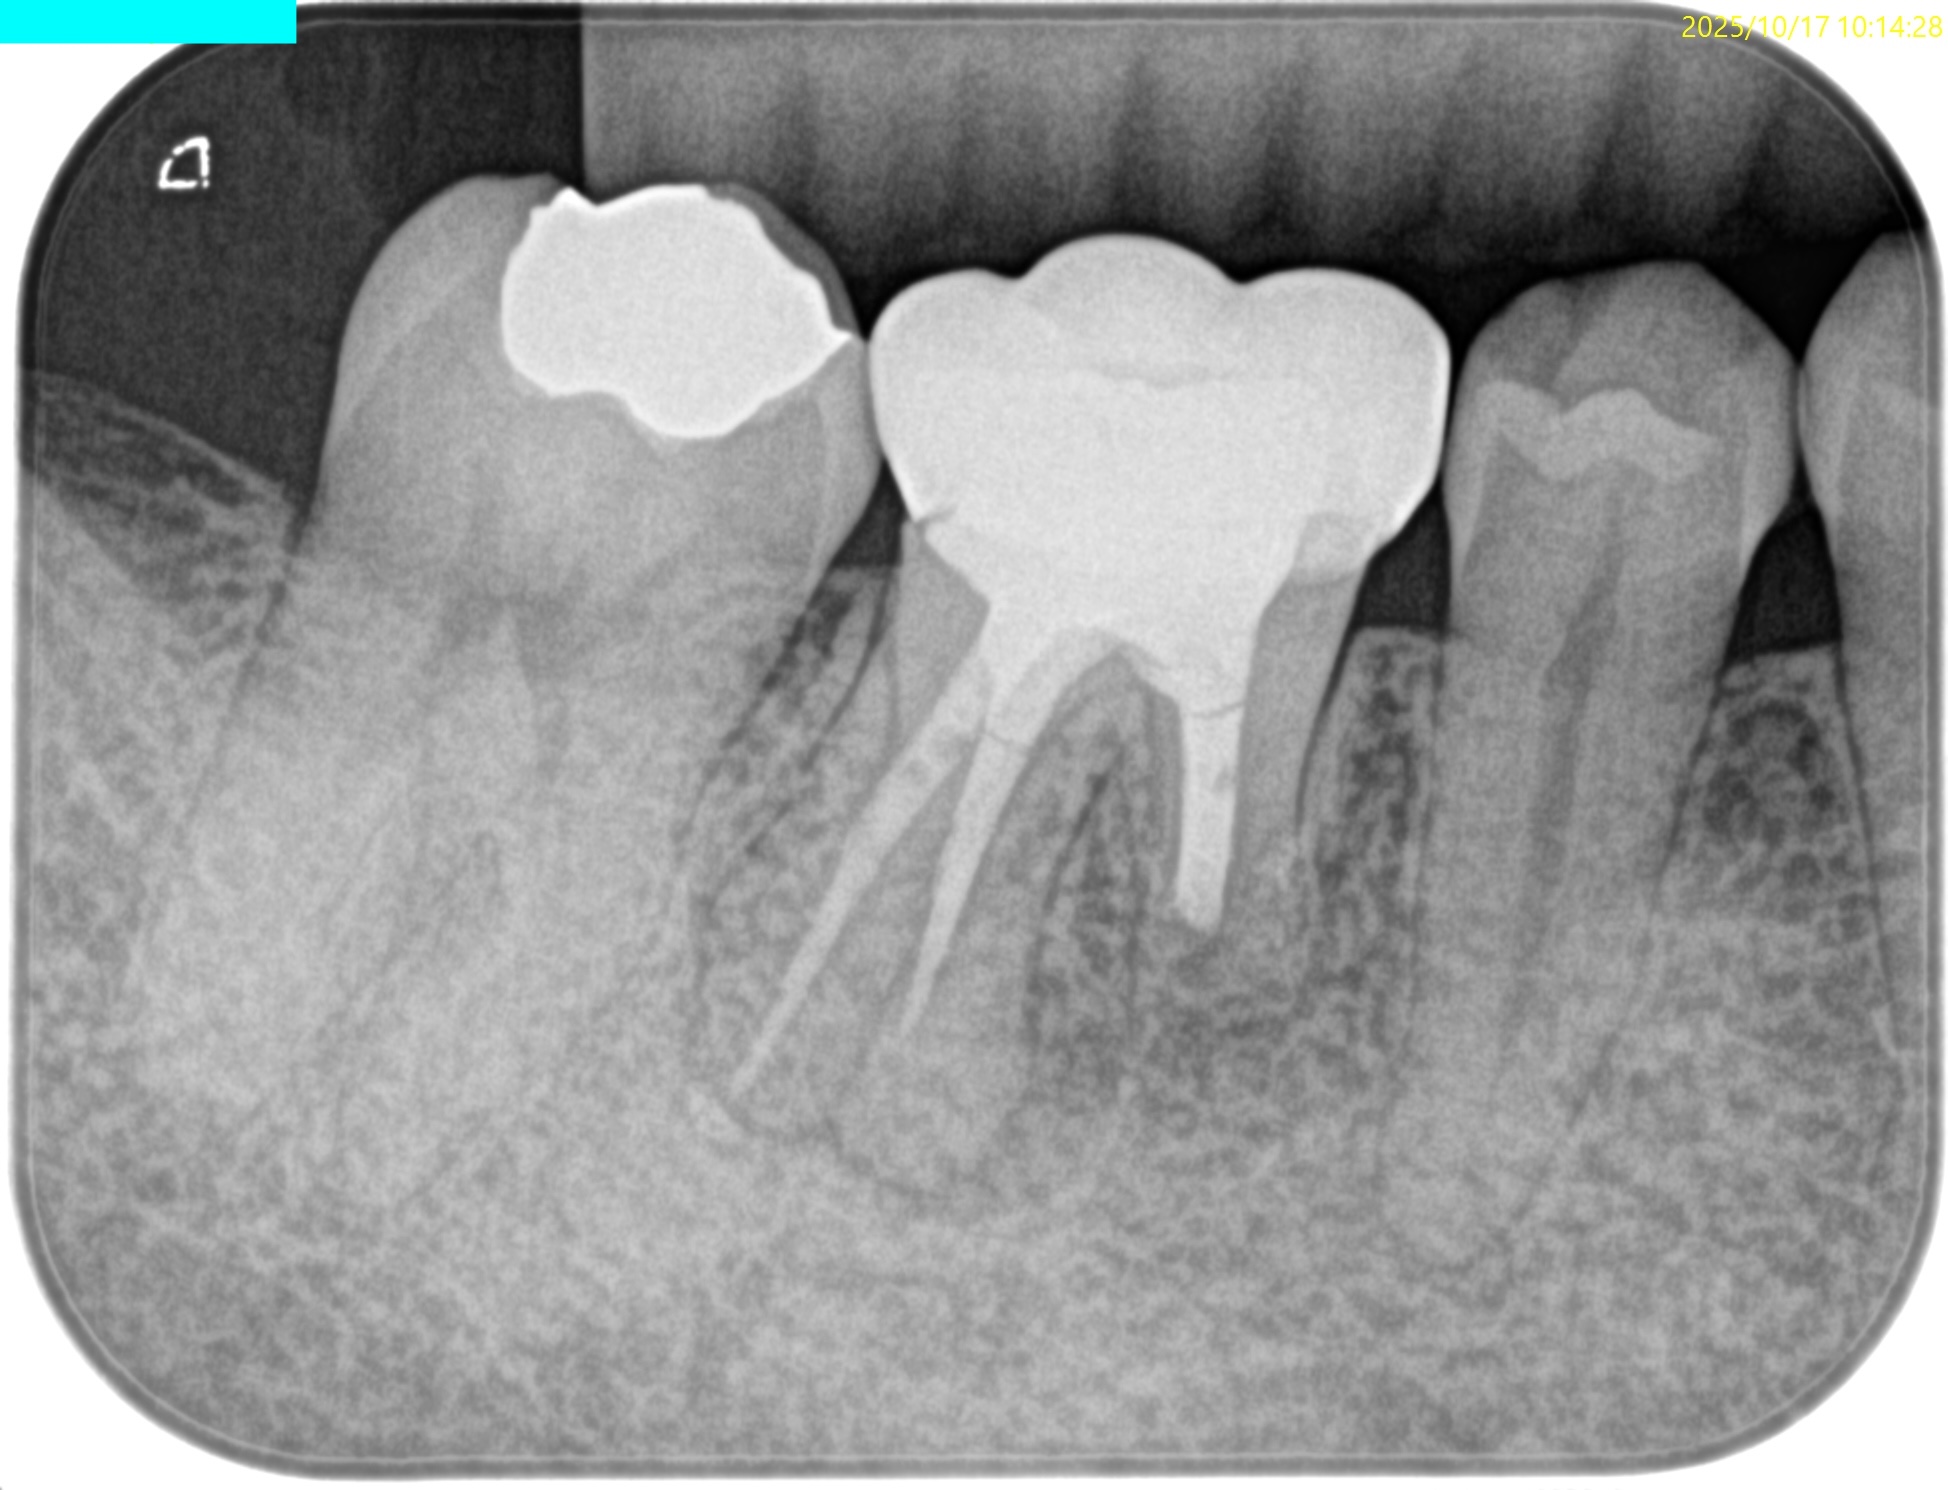

#30 M Apicoectomy, D+Radix Re-RCT 2yr recall(2025.10.17)

M

初診時、1年後と比較した。

トランスポーテーションしたMは劇的に治癒している。

Dも然りだ。

が、トランスポーテーションしているRadixはまだ治癒途中だろう。

が、患者さんに症状もないことからこの歯の状況はさらに2年後に経過を見せてもらうこととなった。